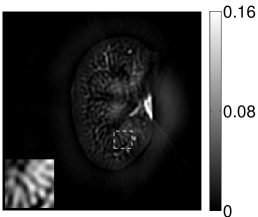

The numerical phantom shown in Figure 1(a) was employed. The phantom had a support area of mm2 and contained six uniform disks that were assigned different values of absorbed optical energy density.

A 2D circular measurement geometry was employed. transducers were evenly distributed on a ring of radius mm that enclosed the phantom. The SOS was assumed to be constant and set at mm/s. Since the simulated data were formed by use of the C-D imaging model in Eqn. (2), no inverse crime was committed. The components of this vector corresponded to equally spaced temporal samples over the interval s. Subsequently, the noiseless voltage vector was obtained by convolving the pressure data with EIR-1 in Figure 1(b).

The reconstruction region ( mm2) was represented by pixels with pixel size mm in each dimension. The initial guess of the EIR employed in the VP algorithm was different than the EIR that was assumed when generating the simulated data. This served to simulate a situation in which an experimentally measured EIR contained errors.

Each element in a real-world transducer array possesses its own EIR. In practice, the differences between the EIRs are sometimes neglected and an EIR corresponding to a single element may be used to represent all elements in the array. In some of the studies below, the EIR employed to initialize the VP algorithm (EIR-2 in Figure 1(b)) and the EIR employed to produce the simulated measurements (EIR-1 in Figure 1(b)) were experimentally measured from two different transducer elements in a circular transducer array (see Sec. VI-B). EIR-1 was measured by temporally integrating the PA signal produced by a point source positioned at the focus of the transducer. EIR-2 was measured by use of the method reported in [RNR2011]. In order to investigate the sensitivity of the VP algorithm to the initialization of the EIR, we employed different EIRs obtained by degrading EIR-1 as described later. When solving the sub-problem in Line-2 of Algorithm 1, was initialized as the zero vector. Algorithm 1 was terminated after 500 iterations, since it was observed that the changes in the reconstructed images with more iterations were negligible. When implemented by use of a single core of an Intel Xeon E5-2640 CPU, each iteration required approximately 7s to complete.

Figure 2(a) shows the image reconstructed by use of the conventional iterative method that utilized a system matrix based on EIR-2. Different values of the regularization parameter from the interval were considered. The reconstructed image with the value of that minimized the RMSE was chosen to represent the best performance of the conventional iterative method. Figure 2(a) and the profile in Figure 2(c) demonstrate that the use of an inaccurate EIR can result in strong artifacts and distortions in images reconstructed by use of the conventional methods.

When the VP algorithm was applied, different values of the regularization parameter from the interval and from the interval were considered. The image that minimized the RMSE was chosen and displayed in Figure 2(b). As revealed by this image and the profiles in 2(c), the VP algorithm yielded an image with fewer artifacts and distortions, and image fidelity was improved as reflected by the reduced RMSE.